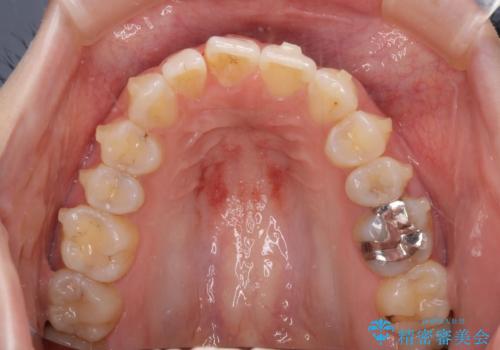

- 矯正治療の後戻りが気になるとのことで来院された患者様です。

上顎の後戻りをインビザライン・ライトで治療することとしました。

上顎のみの治療を希望されたため、咬み合わせをしっかりと改善することはできませんでしたが、審美面が大きく改善され、日常生活の機能面でも不具合を感じることはなく、大変満足していただきました。